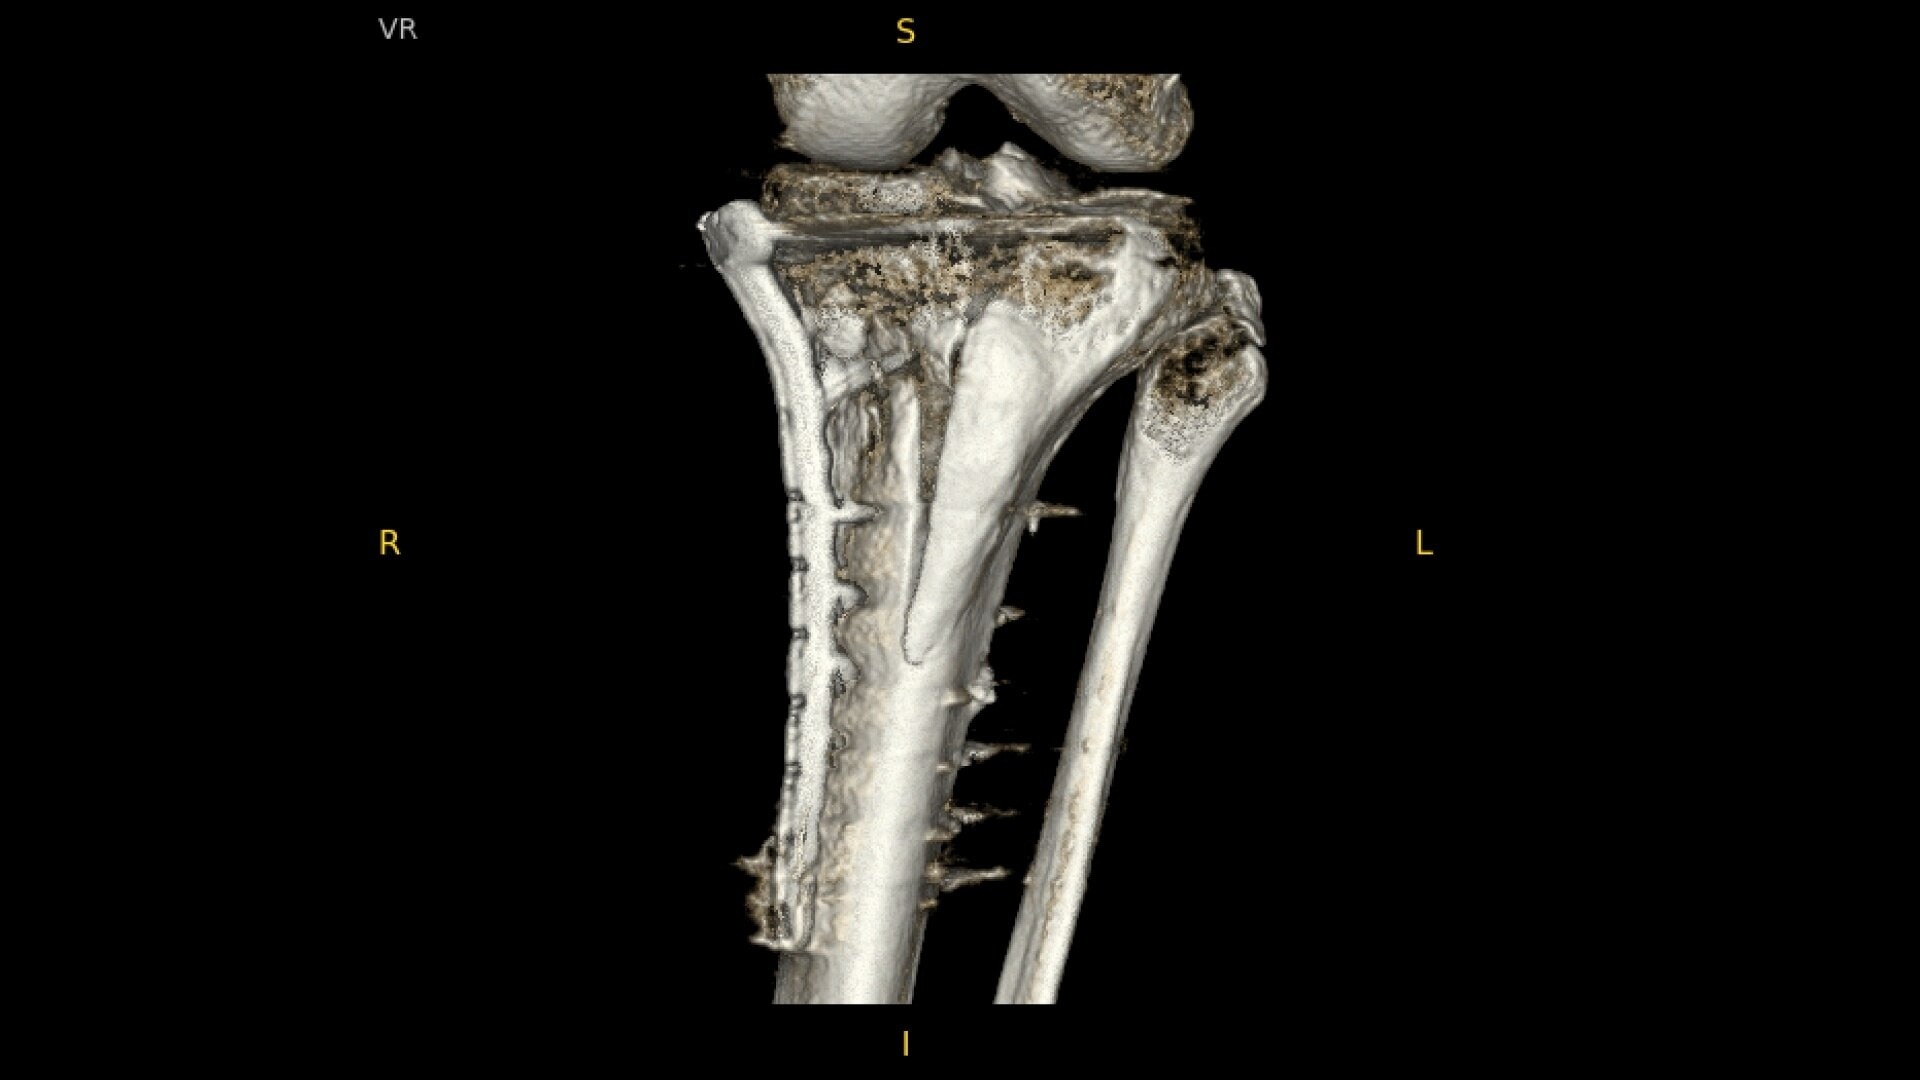

OEC C-arms provide orthopedic imaging with a large field of view optimized to clearly visualize orthopedic anatomy, such as the entire long bone femur or minute fractures in extremities. A clear display with comfortable viewing can easily show AP and lateral views, enabling efficient procedure planning.

Live Zoom up to 4X during a fluoro without the additional dose of Mag modes to assess orthopedic fractures and fixations.

See precise anatomical detail of varying densities such as bone and soft tissue with a high dynamic range with the OEC Elite CFD with a flat detector, image processing advancements and 4K viewing display.

Complex orthopedic procedures require powerful imaging systems. OEC premium C-arms perform in a variety of procedures such as:

• Pilon fracture fixation